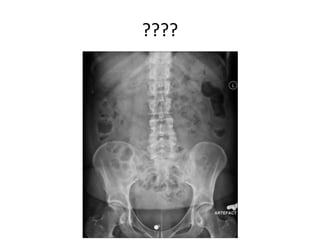

????

• Normal ossal structures on a supine AP image.